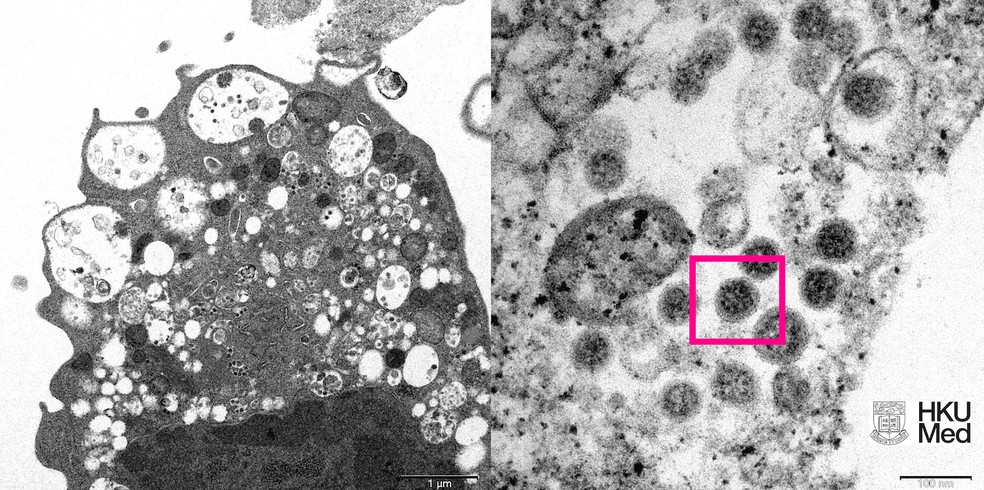

A variante ômicron – também chamada B.1.1529 – foi reportada à Organização Mundial da Saúde (OMS) em 24 de novembro de 2021 pela África do Sul.

O primeiro caso confirmado da B.1.1529 foi de uma amostra coletada em 9 de novembro de 2021. De acordo com OMS, a variante apresenta um “grande número de mutações”, algumas preocupantes.

“Evidências preliminares sugerem uma alta no risco de reinfecção com a variante, comparada com as outras versões do coronavírus”, disse a agência de Saúde das Nações Unidas em um comunicado.